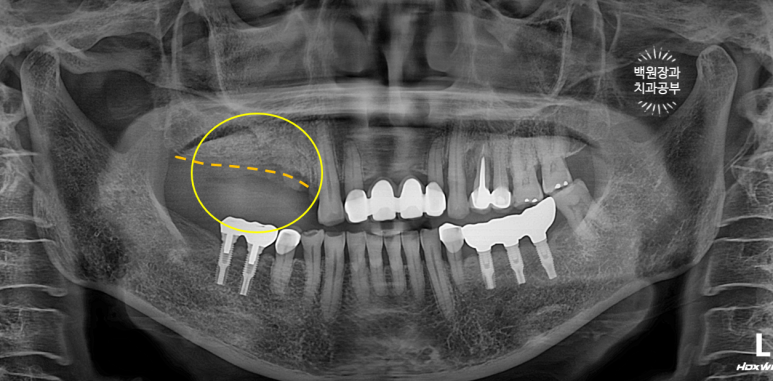

오른쪽 위 임플란트 2개를 약 10년 전에 수술하신 분입니다.

노란색으로 동그라미 쳐져 있는 부위의 임플란트 주변 잇몸에서 고름이 나온다고 하셨어요.

이미 잇몸뼈는 주황색 선처럼 매우 많이 사라져 버린 상태..... 이미 임플란트 주변 뼈는 모두 사라져 빠지기 직전.

보시면 녹색 별로 표시한 자기치아도 주변 뼈가 이미 많이 없어진 것을 보실 수 있습니다.

임플란트 주위염이 심해지면 주변 자연치아도 못쓰게 됩니다. 정기검진을 꼭 다니셔야하는 이유입니다.